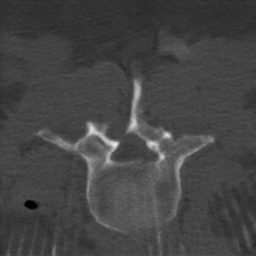

Cone-beam computed tomography (CBCT) has been widely used in spinal surgery as an intraoperative imaging modality to guide the intervention [19, 20]. However, compared with conventional CT, intraoperative CBCT images have pronounced noise and poor tissue contrast [13, 15]. Moreover, it is common to have metallic objects (such as pedicle screws) present during operation, which cause metal artifacts and degrade the quality of CBCT images [12]. To facilitate spinal surgery planning and guidance, it is of great importance to accurately identify the vertebrae [1]; yet the poor CBCT image quality makes it challenging to delineate the vertebra shape even manually.

This paper aims to design a computational method to automatically segment vertebrae from clinical CBCT images, not from cadaver images as in [12]. Since it is challenging to create a large number of CBCT images with annotations and yet high quality (artifact-free and high contrast) spinal CT datasets with vertebra delineations are easy to access [17], we investigate the feasibility of learning a CBCT vertebra segmentation model using unpaired CT images with annotations as in Fig. 1. Such learning has to overcome two obvious gaps: (i) the modality gap between CT and CBCT, that is, the image appearances look different even for the same content; and (ii) the artifact gap as the CT image is artifact-free and the CBCT is artifact-laden. In other words, we have to address three heterogeneous tasks of vertebra segmentation, artifact reduction, and modality translation all together in order to derive a good solution.

Disentanglement and explicit shape constraints. As shown in Fig. 4, we can see streak metal artifacts nearly everywhere in . M1 can roughly disentangle artifacts and anatomical information but strong vertical artifacts and strange air area appear in (see red arrows of M1 in Fig. 4). For the anatomical structure, M1 learns to segment vertebrae with fully supervised and applied on various CT images, but fails to suppress the false bony structure in and as may misclassify some metal artifacts as bone.

Modality translation and artifact reduction. Here we compare our model with other methods: CycleGAN [21], DRIT [8], ADN [9]. All the models are trained with our data using their officially released codes. Further, we train a UNet segmentation network using annotated CT data and apply it to synthesized CT images as an anatomy-invariant segmentation evaluator. As shown in Table 2(b), our model achieves the best performance with a much larger average Dice compared with other methods. Fig. 6 shows the synthetic images and segmentation results. CycleGAN and DRIT tend to output plausible and realistic CT images but are not able to preserve the anatomical information precisely. As shown by the red arrows in Fig. 6, the bony structures appear distorted and noisy. ADN can retain most of the anatomical information but not for the bone pixels with high intensity, which might be classified into metal artifacts. With anatomical knowledge learned from the CT domain, our model outputs high-quality synthetic CT images while keeping anatomical consistency.

For artifact reduction, ADN and DRIT [8] could not successfully recover the clean images and streak artifacts remain in the synthetic image (see blue arrows in Fig. 6). CycleGAN [21] could output clean images but the distorted bones make them less valuable. Our model can suppress all the artifacts and keep the bone edges sharp, which outperforms all the other methods.